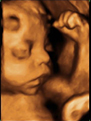

Ecografía 4D de feto de 29 semanas de embarazo

Con 29 semanas de gestación, el bebé ocupa gran parte de la cavidad uterina. En esta exploración ecográfica vemos con gran nitidez el perfil de un feto en el tercer trimestre de embarazo. Incluso se atisban los sutiles movimientos de la boca y barbilla. Los brazos están adelantados en la clásica postura fetal.